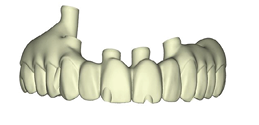

These new records along with the Nexus scans taken at the time of implant surgery were sent to Osteon Medical through the Nexus iOS portal with instructions to replicate the provisional restoration design with correct adaptation to the healed soft tissue. Three days after the data was submitted to Osteon Medical, .STL files of the final design for the maxillary and mandibular restorations were sent through the portal to our office and 3D printed in our office (Figs. 23A-C).

Fig. 23A

Fig. 23B

Fig. 23C